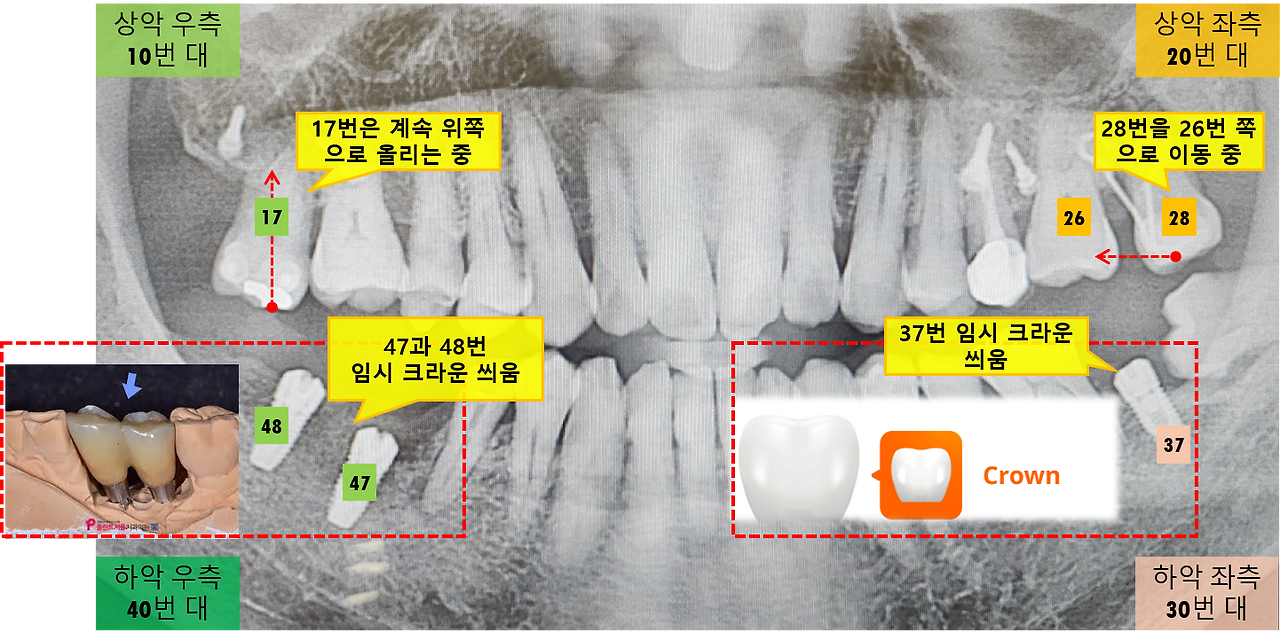

모든 임플란트 임시 크라운 부착.png [임시 크라운 및 교정 중인 치아]

이번 진료는 교정 중인 치아와 임플란트 임시 크라운이 제대로 교합하는지를 확인한다고 합니다. 왼쪽 아래 37번 치아(어금니)와 위쪽 28번 치아(어금니)가 제대로 맞물려 음식을 씹는데 문제가 없는지를 교합지를 사용하여 확인하였습니다. 위아래 교합 상태도 좋아졌다고 하는데 저 역시 교합으로 인한 통증을 거의 못 느끼기는 하네요.

그리고 지난주에 임시 크라운을 씌운 우측 아래 47번과 48번 치아와 위쪽 17번 치아의 교합력도 확인을 하였습니다. 역시 교합상태는 문제가 없는데 치아를 악 다물었을 때 아직은 위쪽 17번 치아에 자극이 있기는 합니다. 이는 오랫동안 사용하지 않던 치아에 갑자기 힘이 가해지면 치주인대가 민감하게 반응하며 통증이 생길 수 있다고 합니다.